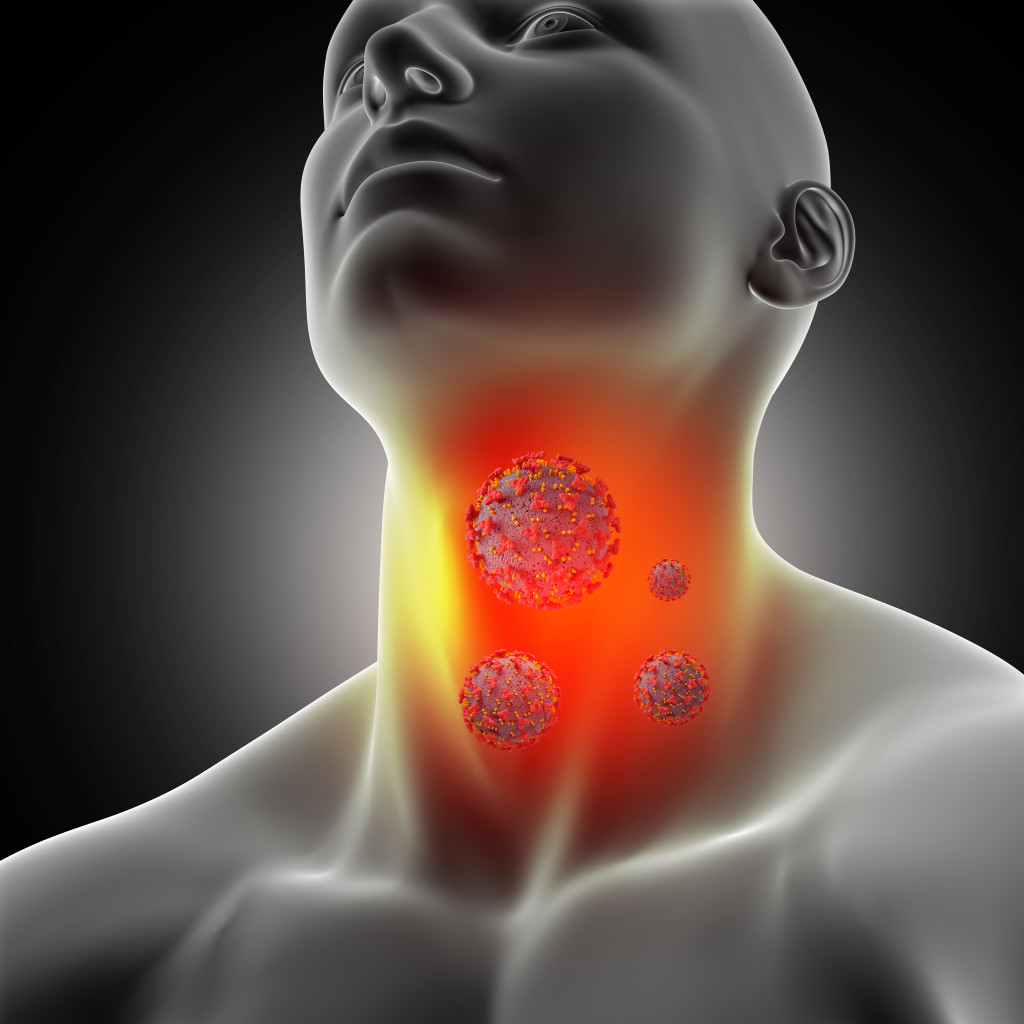

Как курение разрушает организм изнутри Когда речь заходит о вреде курения, большинство людей сразу вспоминает про «рак легких» и «кашель курильщика». Однако воздействие табачного дыма на организм гораздо глубже и системнее. Это не просто вредная привычка, а медленно развивающаяся катастрофа, которая затрагивает каждую клетку тела. Что именно происходит с человеком, который регулярно вдыхает табачный […]